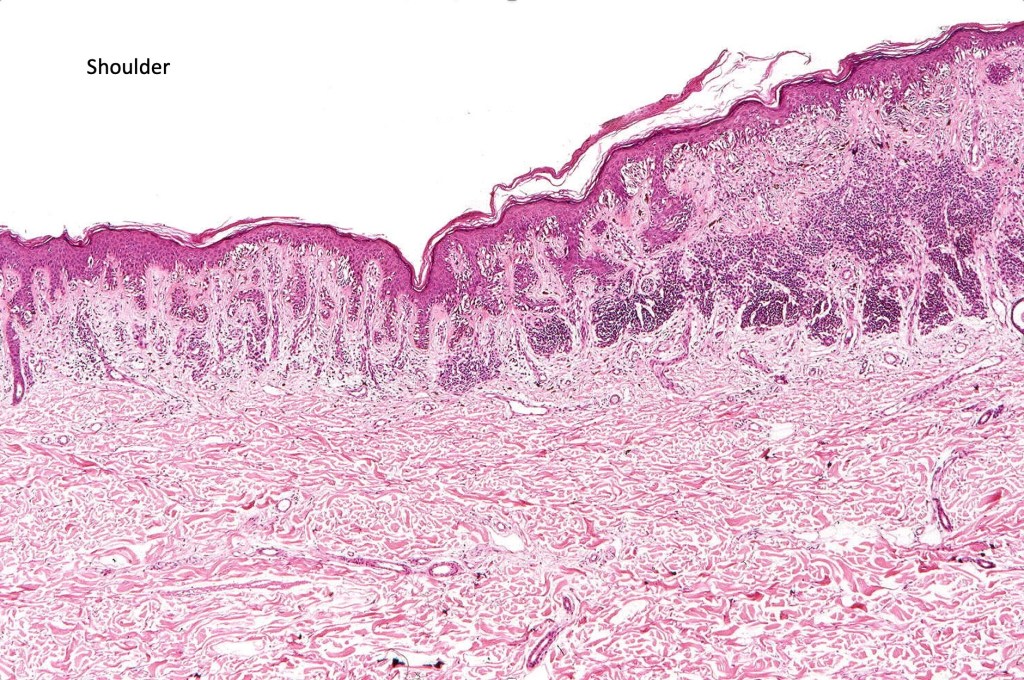

•Shoulder when compound

•Architectural disorder- lentiginous and nested, nests abnormally located (at the sides of the rete ridges & overlying the dermal papillae in addition to the tips of the rete ridges rather than solely occupying the tips of the rete ridges as is seen in banal nevi), horizontal orientation & bridging between junctional nests (this should not be confused with bridging between adjacent rete ridge squamous epithelium)